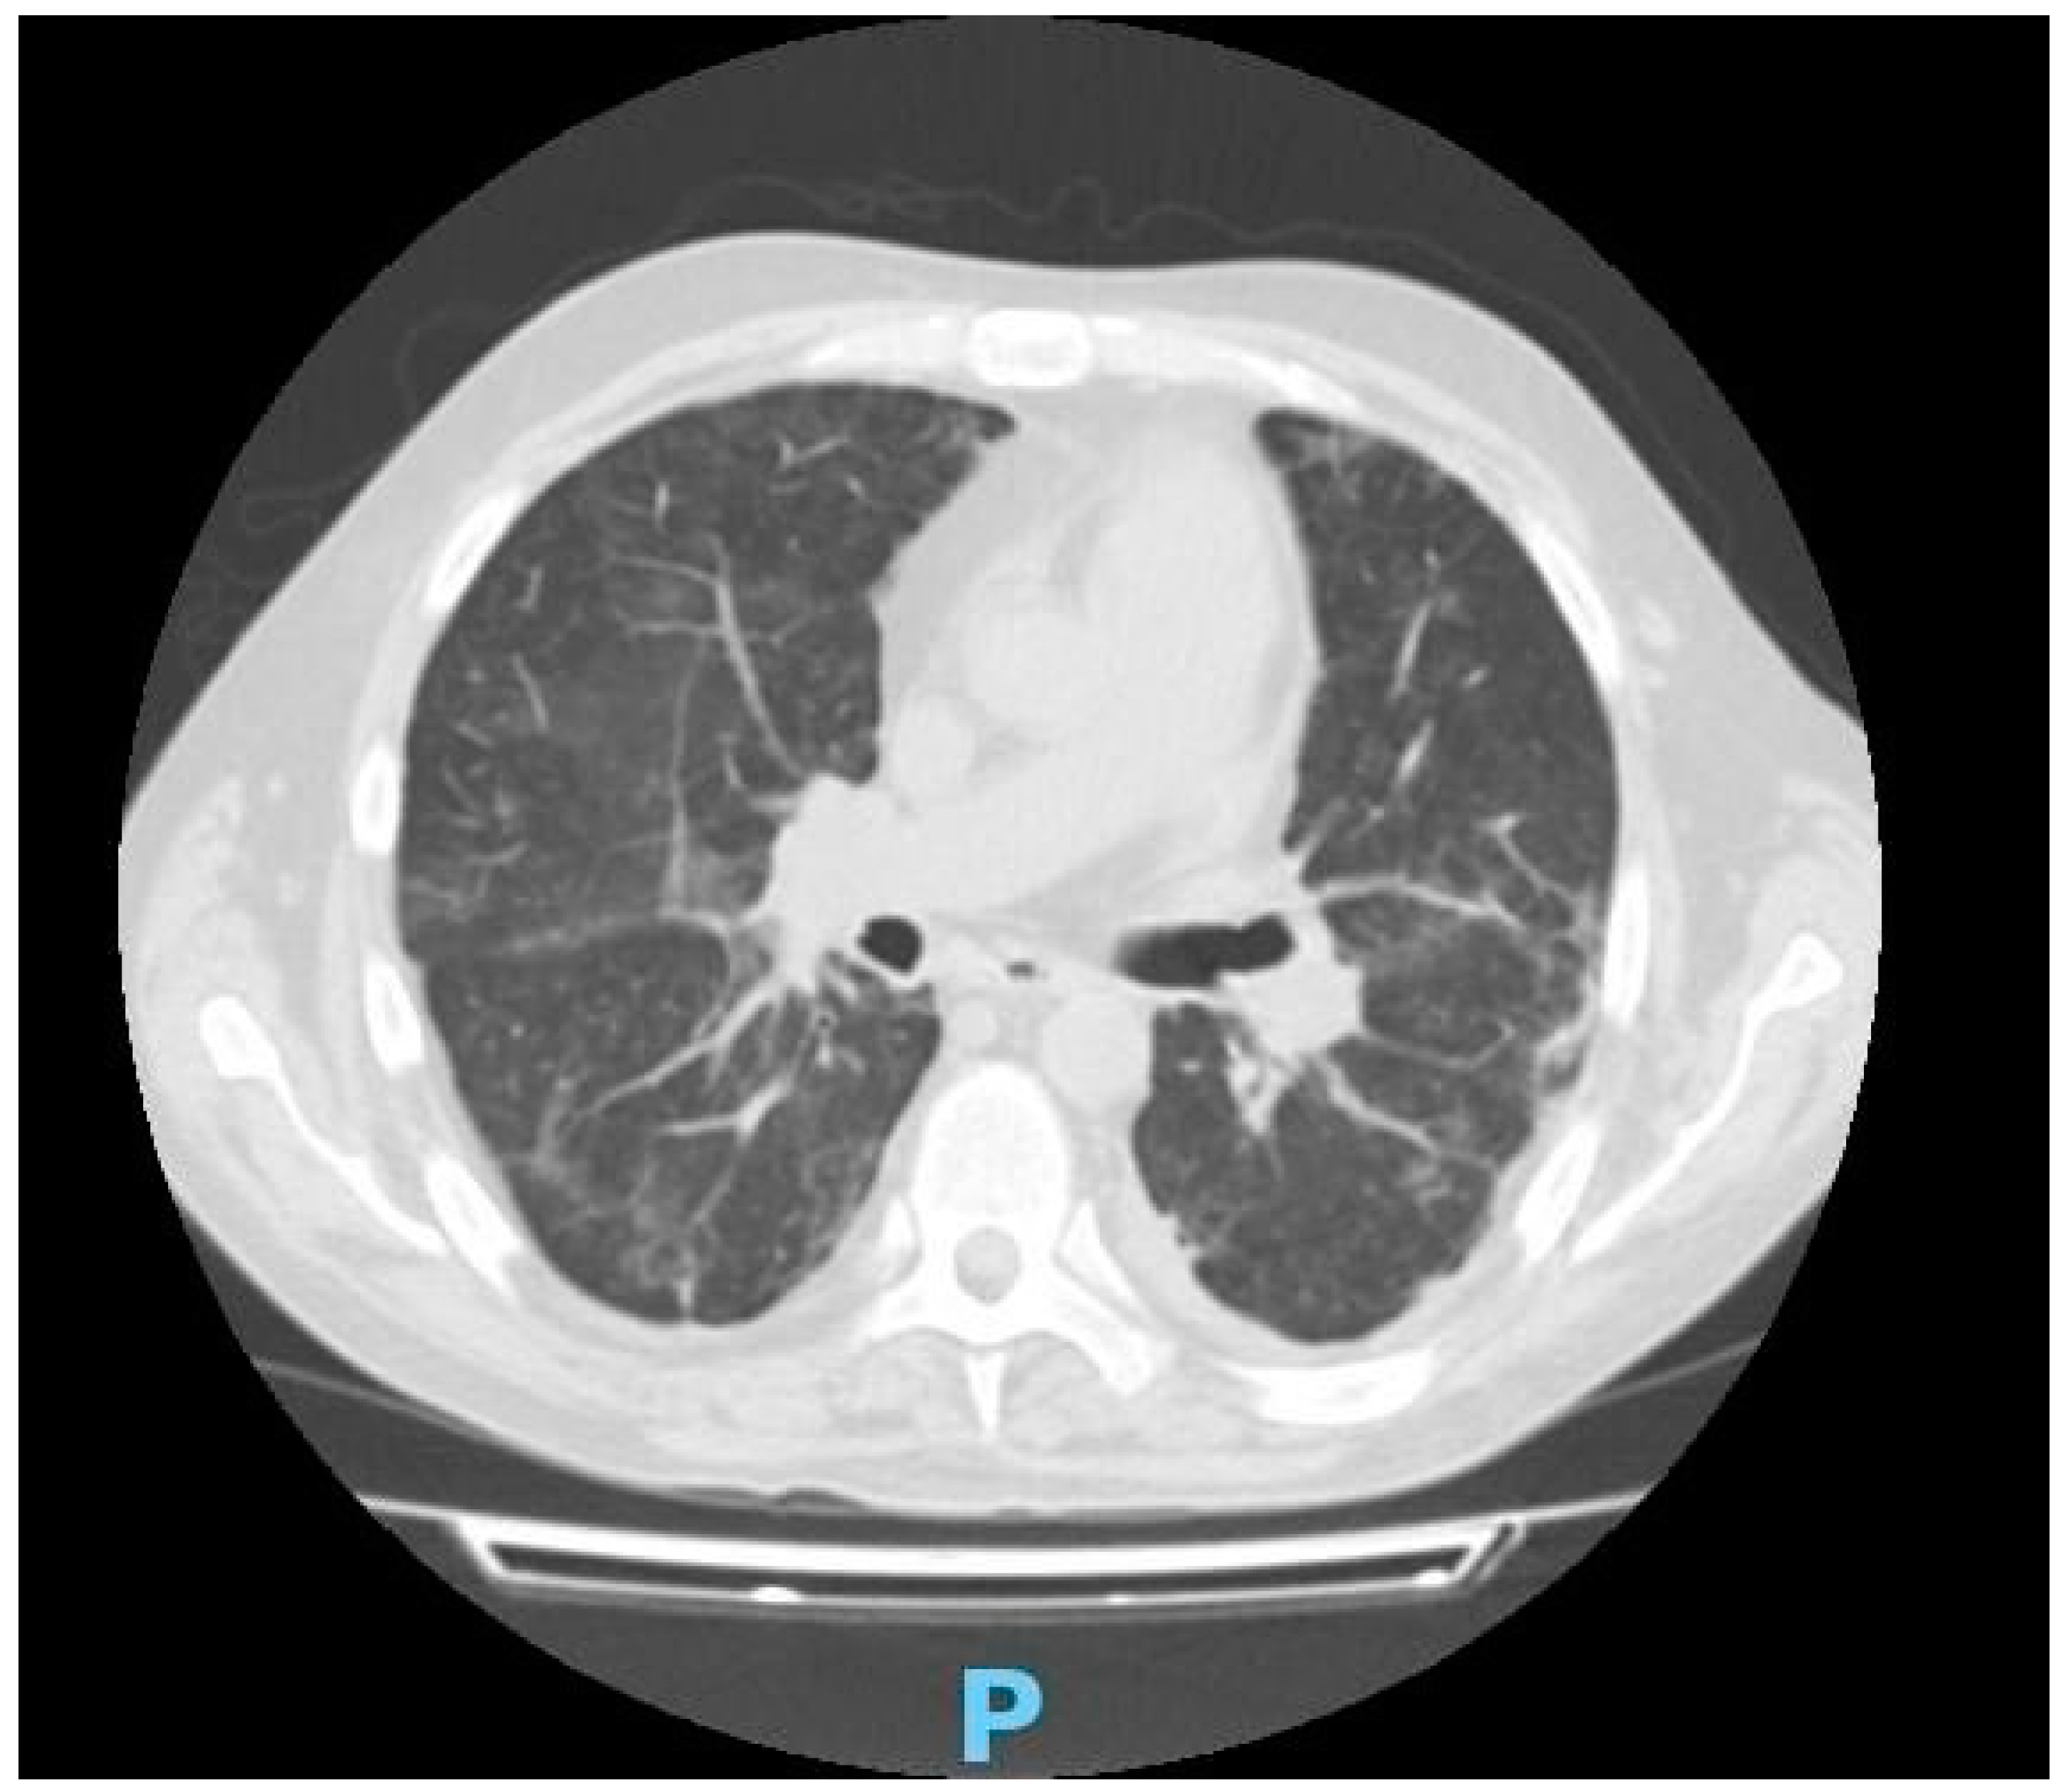

2. Case Presentation